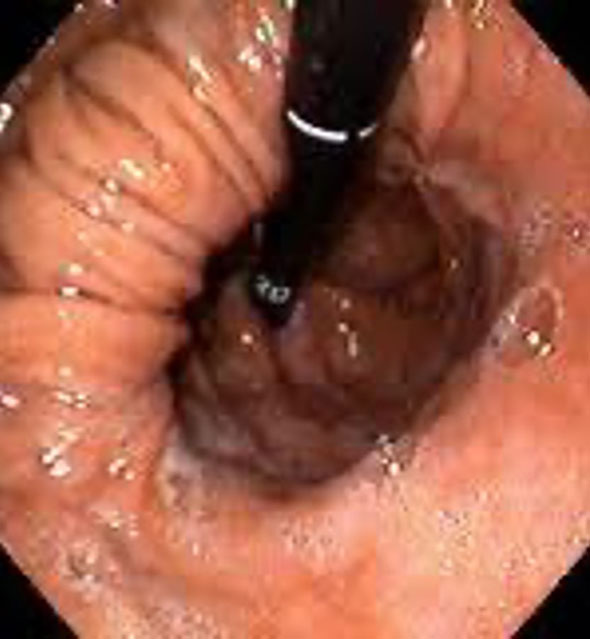

Endoskopide Reflü ile İlgili Ne Görülür?

Reflünün sindirim sisteminde yarattığı hasarı görmenin en kesin yolu endoskopidir. Yemek borusuna kaçan asit hasar yarattıysa bunu görebiliriz.

Yemek Borusu Barrett Hastalığı

Uzun süreli reflü hastalarında ortaya çıkan Barrett Hastalığını, ancak endoskopi sırasında aldığımız doku örnekleri ile ayırt edebiliriz. Mide fıtıklarını görmenin ve kanıtlamanın en doğru yolu da endoskopidir.

Yüksek çözünürlük (HD) en yeni kuşak cihazlarda mevcuttur. Dokuları daha iyi görmeyi ve ayrıntıları yakalamayı sağlar. Narrow Band Imaging (NBI) ise normal ışık dalga boylarını değiştirerek görüntü elde etmeyi sağlar; NBI ile daha derinlemesine görüntü elde edilir.